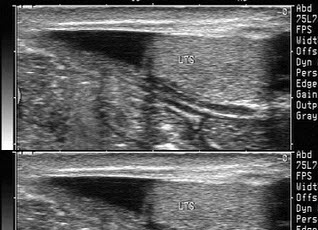

135、单项选择题

某患者舒张期二尖瓣口心动图所示,提示()

A.二尖瓣狭窄

B.二尖瓣关闭不全

C.二尖瓣脱垂

D.正常声像图

E.二尖瓣赘生物